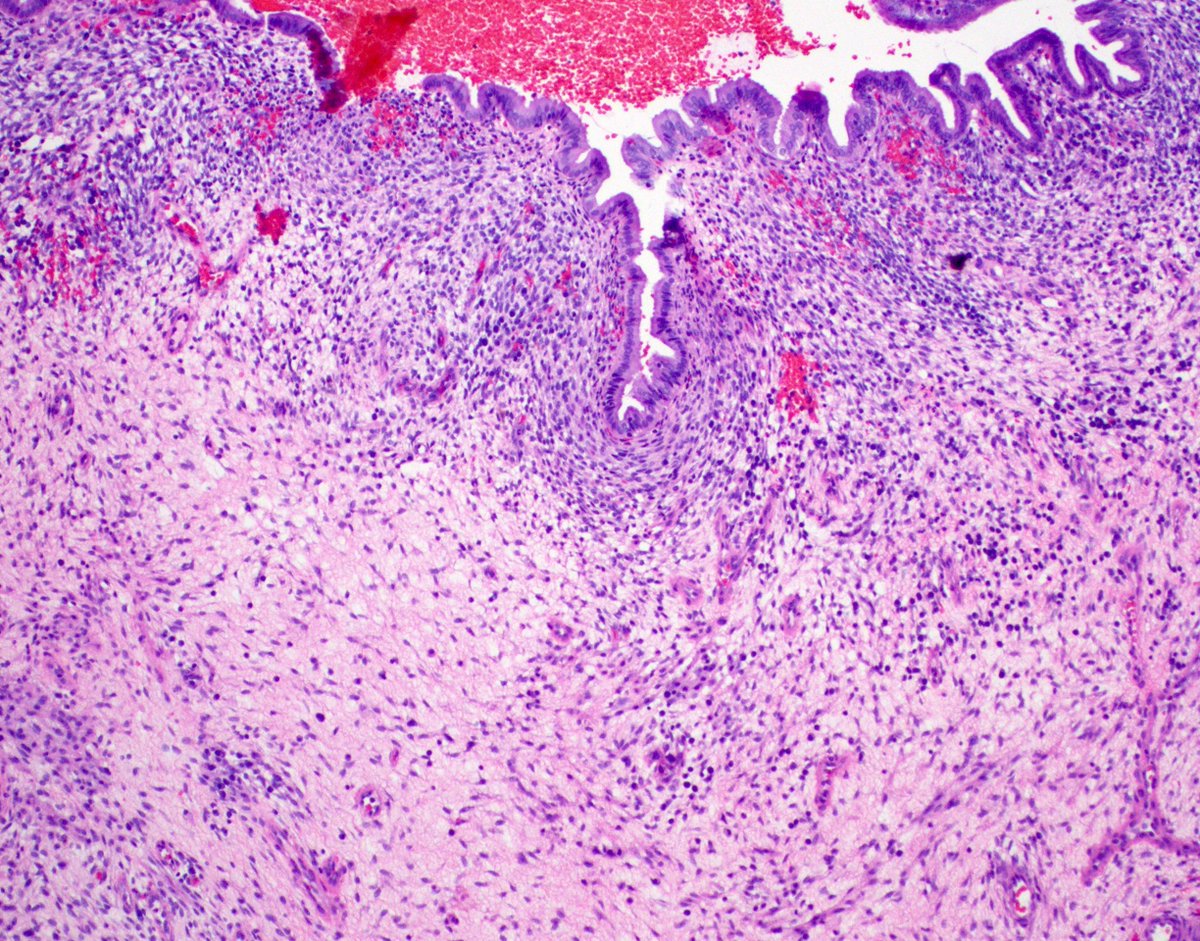

A slow-growing soft tissue mass in a child; histology shows distinctive findings and MUC4 IHC is +. Likely diagnosis? diagnostic gene fusion? #pedipath #softtissuepath #molecpath 🤔🔬🧬